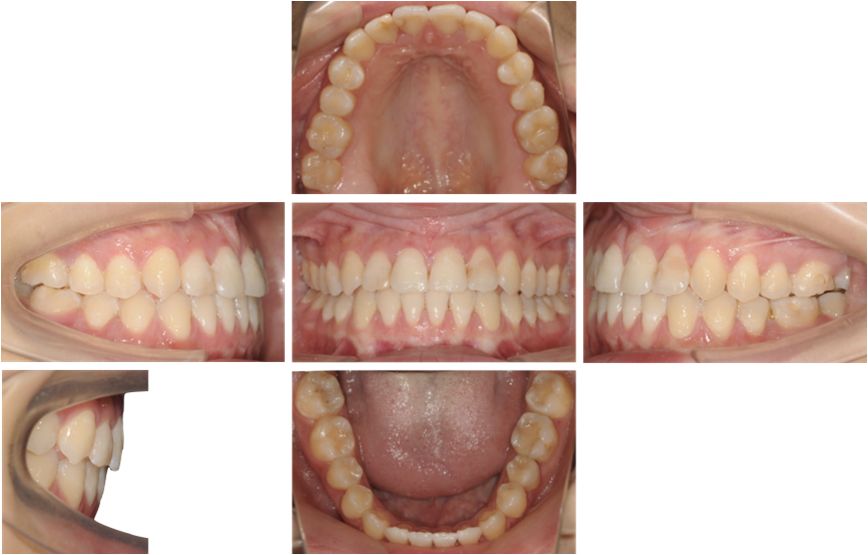

矫治结束

从结束的头影测量分析,看到我们成功代偿了颌骨畸形,前牙角度比较直立。

治疗后全景片显示牙根平行度尚可

右侧颞下颌关节髁突表面骨皮质连续均匀,关节间隙均匀。左侧颞下颌关节髁突表面骨皮质增厚,个别吸收点消失,关节间隙较均匀。

保持3个月的口内像,可以看到矫治效果是比较稳定的。

治疗后头影重叠图可见47牙大量前移关闭拔牙间隙,下颌前上旋转;下前牙少量伸长解决开合,下前牙少量内收、直立。